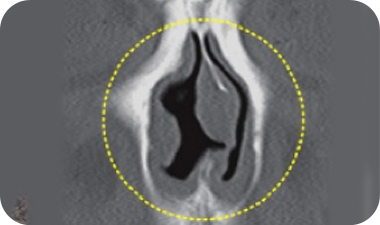

C-shaped septal deviation correction range

S-shaped septal deviation correction range

Deviated Septum

The septum is the vertical wall that divides the two nostrils in the center of the nose.

When the septum is bent or twisted, it is referred to as a deviated septum. Depending on the direction of the deviation, it can be categorized as either a C-shape or an S-shape. A deviated septum can lead to functional issues, such as nasal congestion, rhinitis, and sinusitis.

Surgery Expertise

The surgery is performed by removing the cartilage from the curved portion of the septum and using the remaining cartilage to properly correct the shape and height of the nasal tip.

Before Surgery

Curved Septum

After Surgery

Corrected Septum